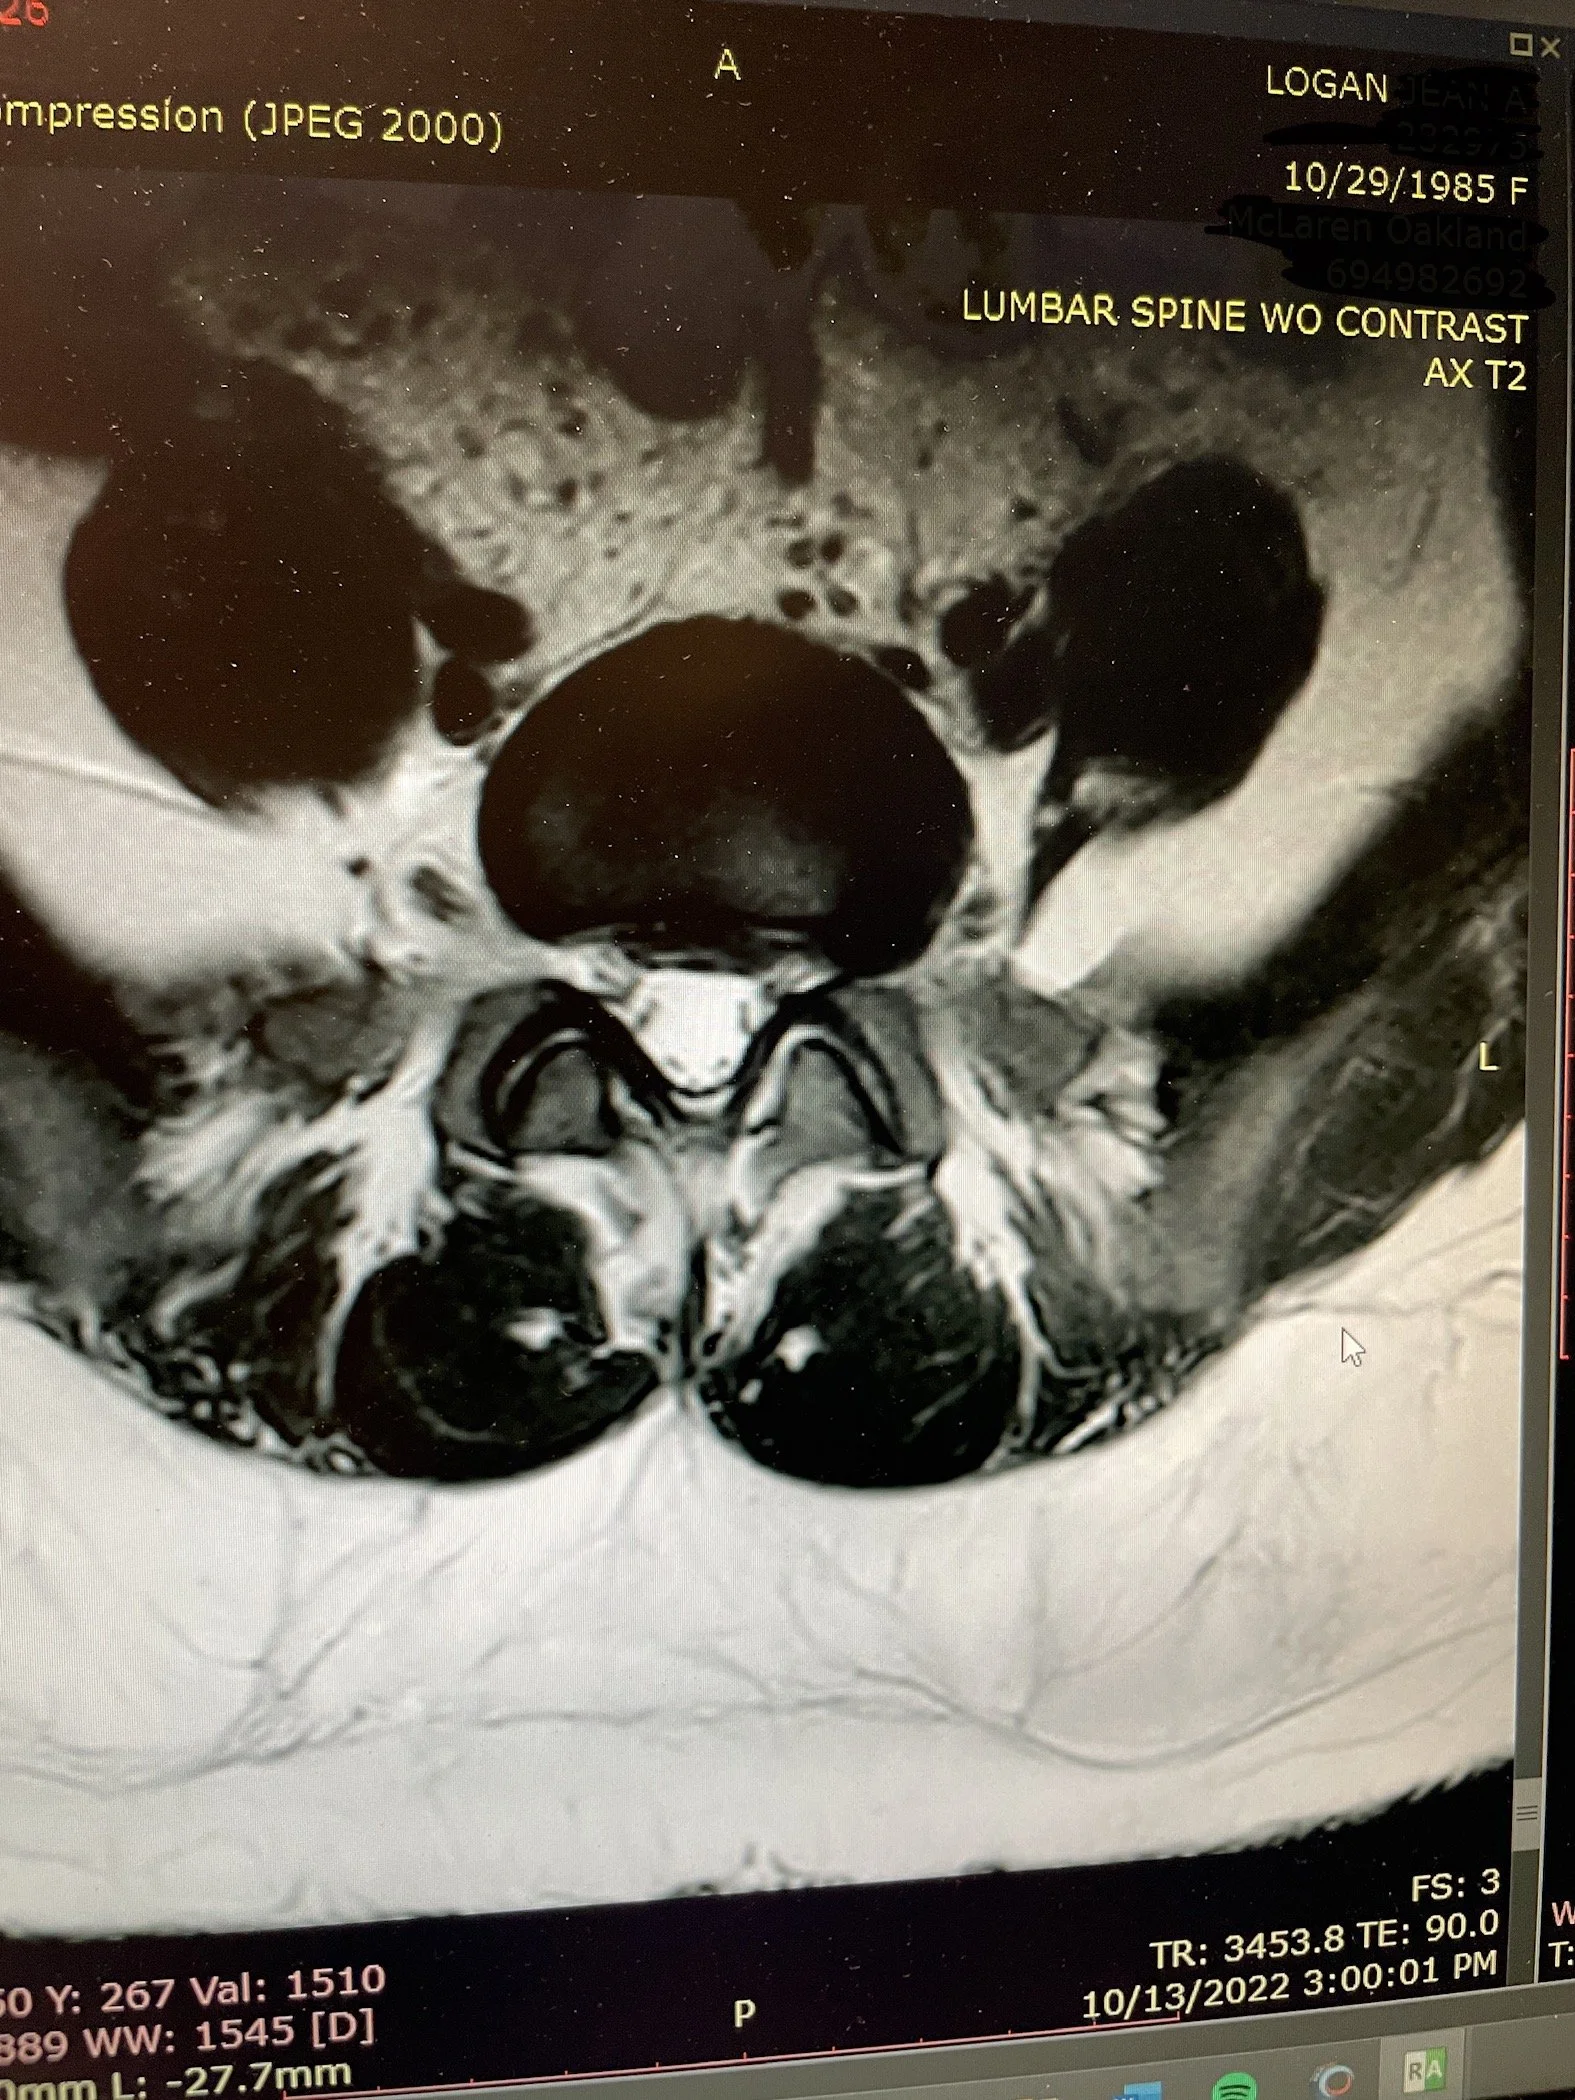

Can I Trade in My Spine?

arthritis